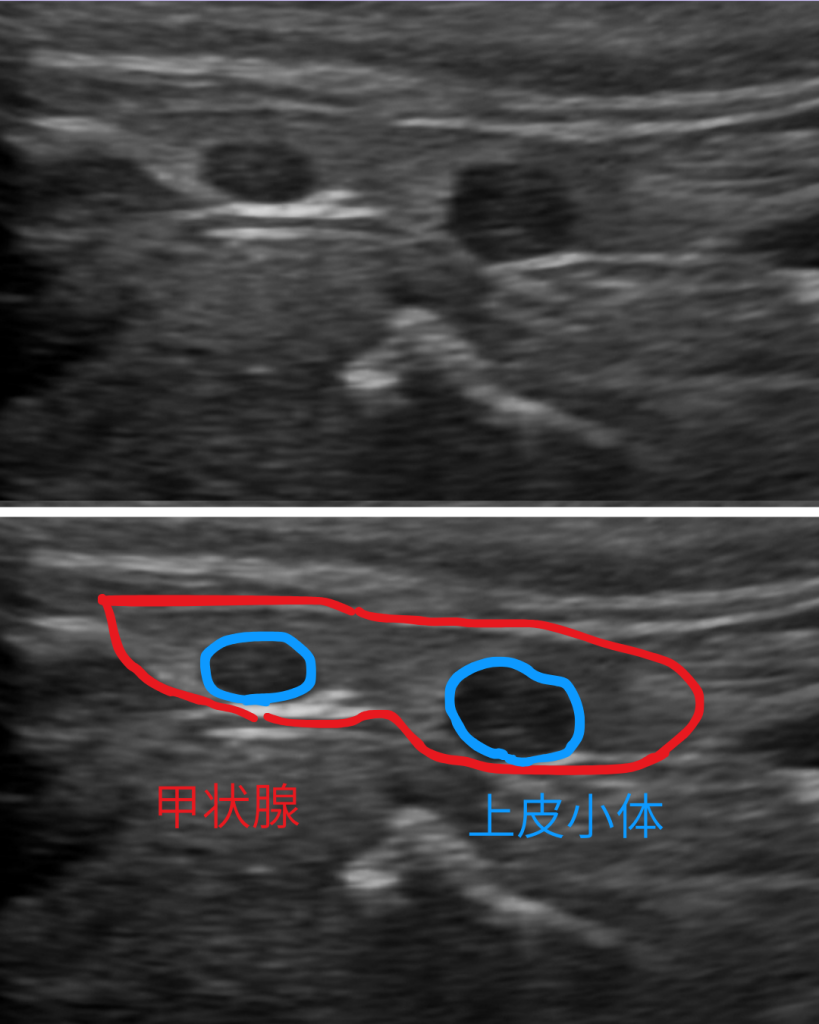

ここである疾患を疑い、頸部の超音波検査も実施しました。通常頸部の超音波検査は、大人しい子でしか実施できない検査で、場合によっては鎮静処置が必要になってきます。この子は検査に協力的な子であったので鎮静なしで検査を実施することができました。

頸部の超音波検査の結果、カルシウムの量を調節している左側の上皮小体という臓器が2か所腫れていることがわかりました。上皮小体は副甲状腺とも呼ばれる臓器で、頸部の甲状腺にくっつくような形で存在しています。ホルモンを出すことでカルシウムの調節をしている臓器です。